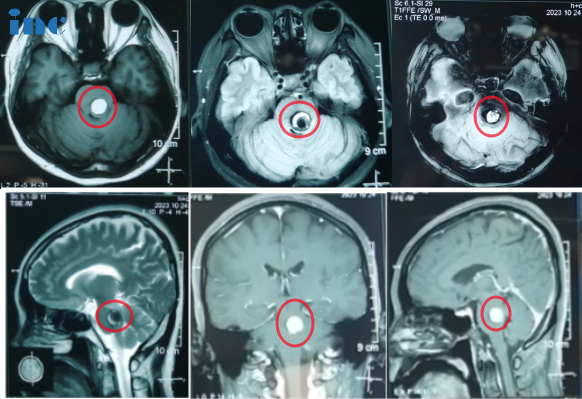

43岁女士--脑干海绵状血管瘤合并出血

2023年的1月,陶女士由于右侧嘴角发麻到医院查出脑干海绵状血管瘤、且脑干部位渗血。当地医院建议手术治疗。北京多家医院就诊,给出的建议都是保守治疗。原因是症状轻,位置深,手术风险大,建议等二次出血后再行手术。回家保守观察后,没有任何治疗,直到10月17日晚,陶女士再次感觉到麻胀感延伸到整个身体。10月再次增强核磁检查,提示再次出血,病灶从原本的1.2cm增大到1.6cm。1年内2次出血,病灶也在增大,现在需要手术吗?陶女士开始焦虑起来……

巴教授是如何为她评估的:“较佳手术时间就是是现在。原因是随着出血脑干会被血肿压迫膨胀,从而形成更大的手术空间,手术的话对周围的颅神经损伤风险会降低。但是随着血肿逐渐被吸收,局部瘢痕组织形成会导致手术难度翻倍增大,这会给患者带来更大的手术风险。在这个位置现在存在大量的血肿,经过手术可以给这个血肿清除掉。我可以为患者提供手术,将脑干海绵状血管瘤完全切除,并且在不出现面瘫的情况。她需要尽快赶往苏州,因为几天后我将会抵达此次中国之行的二站——苏州。”